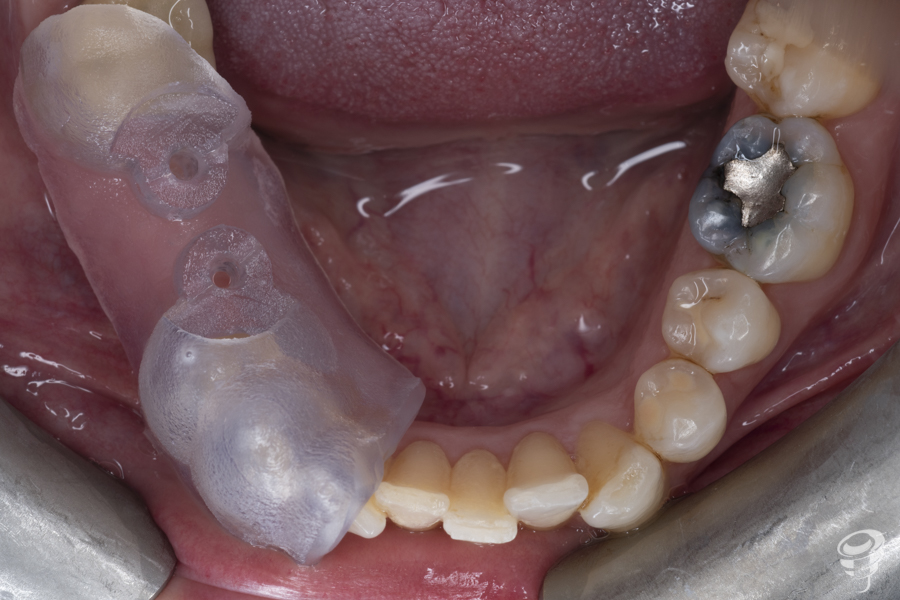

El presente caso clínico tiene como objetivo la rehabilitación de un paciente que presenta edentulismo parcial mandibular en 45 y 46, con la colocación de dos implantes dentales, utilizando una guía quirúrgica para el fresado inicial y posteriormente el uso de osteotómo.

A.M.R Paciente de 40 años de edad, de sexo femenino, edéntula parcial, no fumadora y sin antecedentes médicos de interés. La paciente fue evaluada radiológicamente con una tomografía computarizada de haz cónico y se procedió a la planificación de su caso mediante el sistema informático Galimplant 3D Exacto®. Se planificaron dos implantes galimplant de 4X10mm (IPX 4010).

Guía quirúrgica y secuencia de fresado

Una vez realizada la planificación de los dos implantes, se lleva a cabo la impresión de la férula quirúrgica dento-soportada con dos orificios cilíndricos adaptados a la fresa pin de 2 milímetros de diámetro. Esta fresa tiene la función de guiar tridimensionalmente la posición del implante.